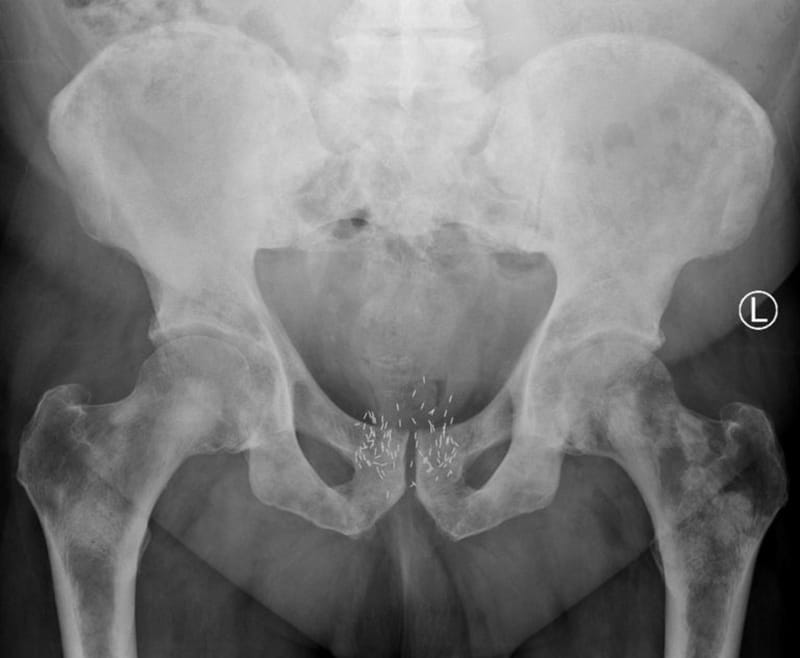

“There are particular challenges in delivering brachytherapy – it’s not the only treatment for prostate cancer, but it’s a good option for treatment for many patients. This development will, we hope, allow medics and scientists to come up with a treatment plan that is much more focused on the individual and the ‘map’ of their particular cancer. It will mean fewer needles need to be used, the treatment will be less invasive, and it will be much more accurate, giving medics superb precision.”

00:03:38 robotised prostate brachytherapy contributes and reducing side-effects erectile dysfunction genitourinary and gastrointestinal oedema and could improve the deposits of radioactive seeds reliability and accuracy the concept can be extended to biopsy operations using the same principle of needle guidance and targets Tracking's